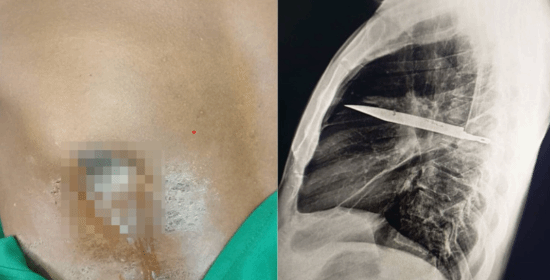

近日,坦桑尼亚出现一起罕见医疗案例,一名44岁男子右侧乳头附近长期流出恶臭脓液,情况反复无法改善,因而前往就医。

医生随即安排胸腔X光检查。画面清楚显示,右肩胛骨位置有一片利刃状金属残留物,从肩胛骨方向刺入胸腔,周围被脓液与坏死组织包围,显示已存在相当长一段时间。

进一步评估后,医生研判这片刀刃极可能是当年冲突时遗留在体内,时间约8年。之所以没有立刻要命,是因为刀刃位置非常刚好,避开了心脏、大血管与主要肺部结构,才让男子这么多年来几乎毫无异状。

在医生安排下,男子立刻接受外科手术,将胸腔内的刀片完整取出,同时清除周边坏死组织与脓液。